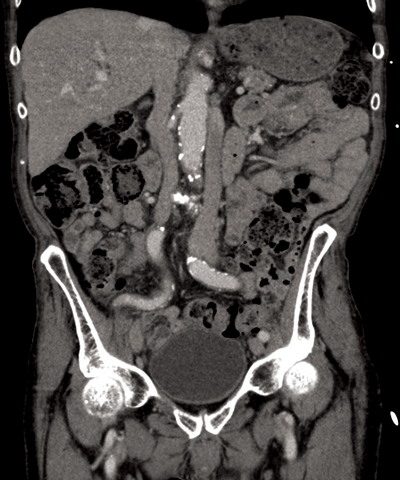

Figure 3: Two left renal veins, one seen anterior to the aorta

and the second seen coursing posterior to the aorta.

Circumaortic renal vein (Figure 3)

There are two varieties of circumaortic renal vein, which overall have a prevalence up to 8.7% [5]. Most commonly the left renal vein bifurcates into two limbs just prior to reaching the abdominal aorta and thus enclosing it [2]. In the remaining 25% the left renal vein duplicates at the renal hilum. The retroaortic limb is positioned more caudally to the preaortic limb, and is often the smaller limb [4]. Usually, the gonadal vein joins the dorsal left branch of the left renal vein, whereas the adrenal vein joins the ventral branch [1].